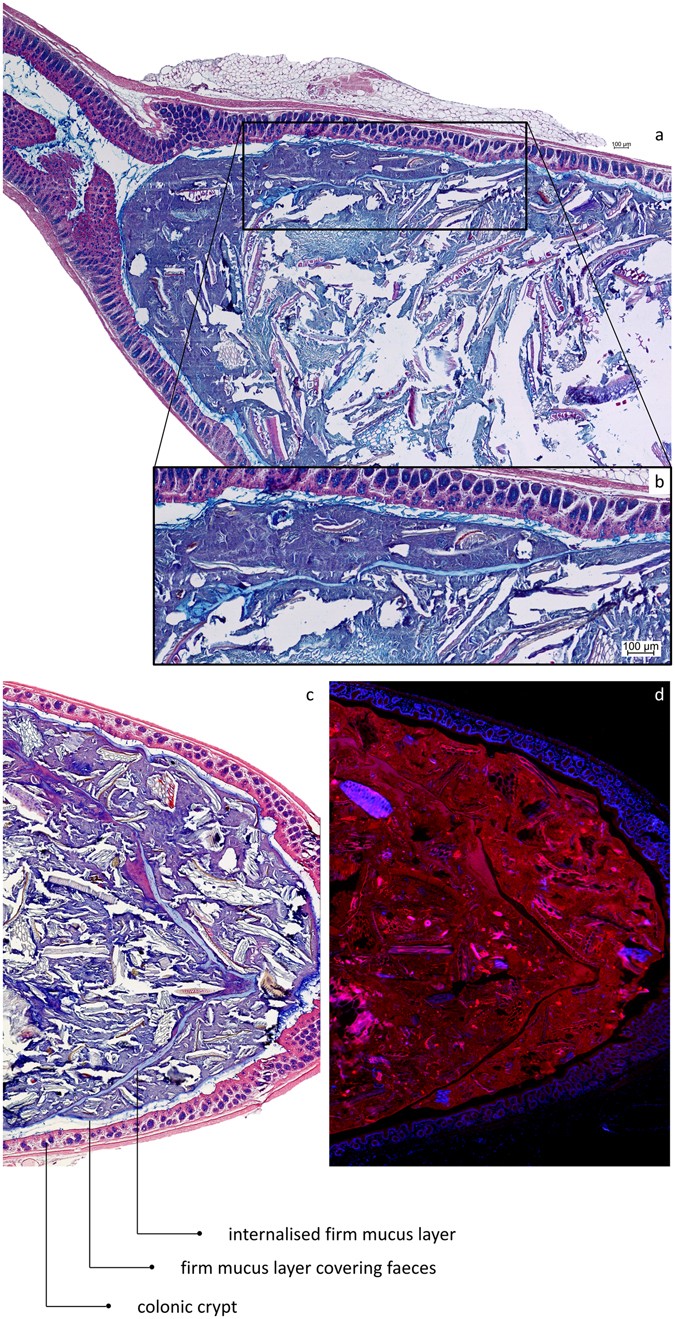

Figure 5

From: Mucus organisation is shaped by colonic content; a new view

After collisions between faecal pellets in the distal colon, the mucus layers covering their surface can be internalised into the resulting composite pellet. (a) AB/H/E stained longitudinal section of distal mouse colon. (b) Close-up showing the internalised firm mucus layer. (c) AB/H/E stained longitudinal section of distal mouse colon. A firm mucus layer devoid of bacteria is found inside the pellet. (d) FISH stained (Bacteria in red; nuclei in blue) longitudinal section of mouse distal colon, the internalised firm mucus layer is recognised by the absence of bacteria.